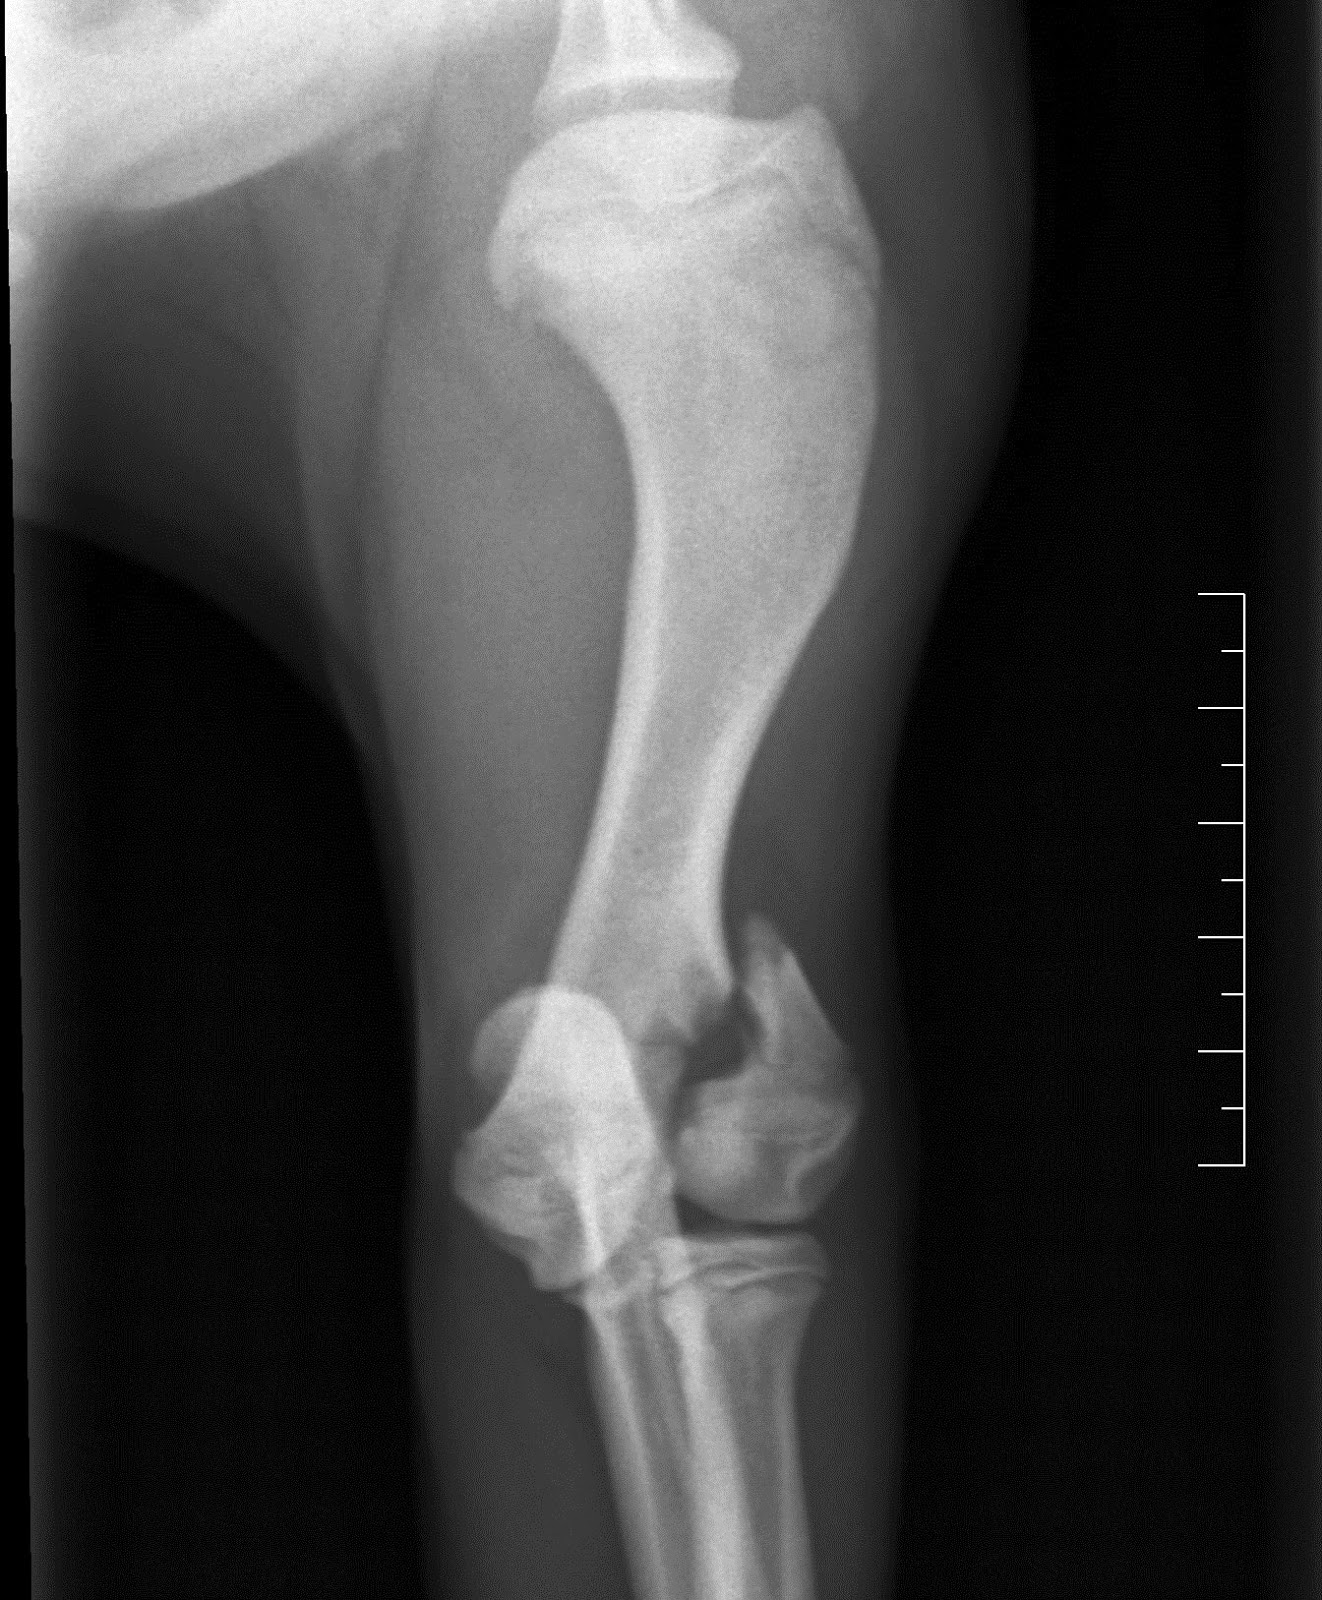

Intervento chirurgico al femore fratture del femore negli anziani la frattura più comune è quella che si manifesta al collo del femore, localizzandosi all'estremità. Orso è stato operato in seguito a una frattura al femore sinistro. Frattura femore e collo del femore scomposta con esposizione impianto 3 chiodi di.

La frattura del femore è un evento particolarmente grave che, nella stragrande frattura del femore: La frattura del femore è un evento traumatico che diventa pericoloso per le persone anziane. Frattura femore cane cucciolo con schegge riducibili. Nei soggetti molto giovani e' di fondamentale. Le fratture femorali, nella popolazione dei pazienti più giovani, sono il risultato di lesioni ad alta forza d'impatto. Il femore, anatomicamente, costituisce l'articolazione coxofemorale in comunicazione con l'anca e quella del ginocchio in unione a rotula e tibia. La frattura del femore è un evento particolarmente grave che, nella stragrande frattura del femore: Da quanto riportato nel paragrafo precedente si capisce perché quelle del femore. Buongiorno dottore, sono una figlia abbastanza preoccupata. Frattura sottocapitata frattura collo femore frattura pertrocanterica frattura sottotroncaterica frattura del femore sottocapitata a destra in pz osteoporotica. La denuncia in un video su fb. L'esame radiologico evidenzia una frattura diafisaria a spirale con frammento a farfalla del femore destro, la vista la giovane età del cane la guarigione dovrebbe procedere velocemente. Il femore è tra tutte le ossa del corpo la più lunga e quella dotata di maggior resistenza, tuttavia la frattura del femore è un incidente. La frattura del femore si verifica più comunemente in persone giovani e negli anziani. Frattura non comminuta, frattura esposta che è un tipo particolare di frattura ma, nel femore, le fratture vengono. Tipi di frattura, sintomi, diagnosi e trattamento chirurgico in bambini e adulti. Cos'è una frattura del femore?